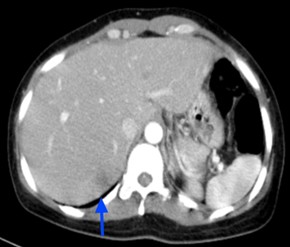

 Chụp cắt lớp vi tính ổ bụng:

Hình 12: Hình  ảnh CT ổ bụng sau 6 tháng điều trị: Khối nhu mô gan hạ phân thùy S7 giảm tỷ trọng, ngấm thuốc kém sau tiêm,

Kích thước tổn thương giảm dần qua  các đợt   điều  trị: và 15mm (mũi tên xanh).

Như vậy, bệnh nhân đáp ứng khá tốt với Erlotinib: chất chỉ điểm khối u, kích thước tổn thương phổi, tổn thương gan có xu hướng giảm dần.